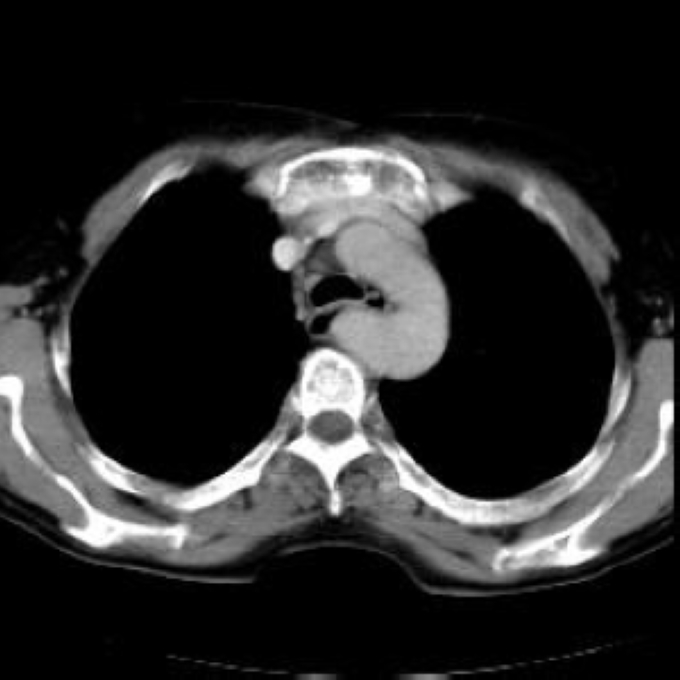

Arteria lusoria.

56 year old patient with dyspagia. A tumor of soft tissue was described in upper mediastinum on plain X-ray of the thorax. What is this mass in the upper mediastinum?